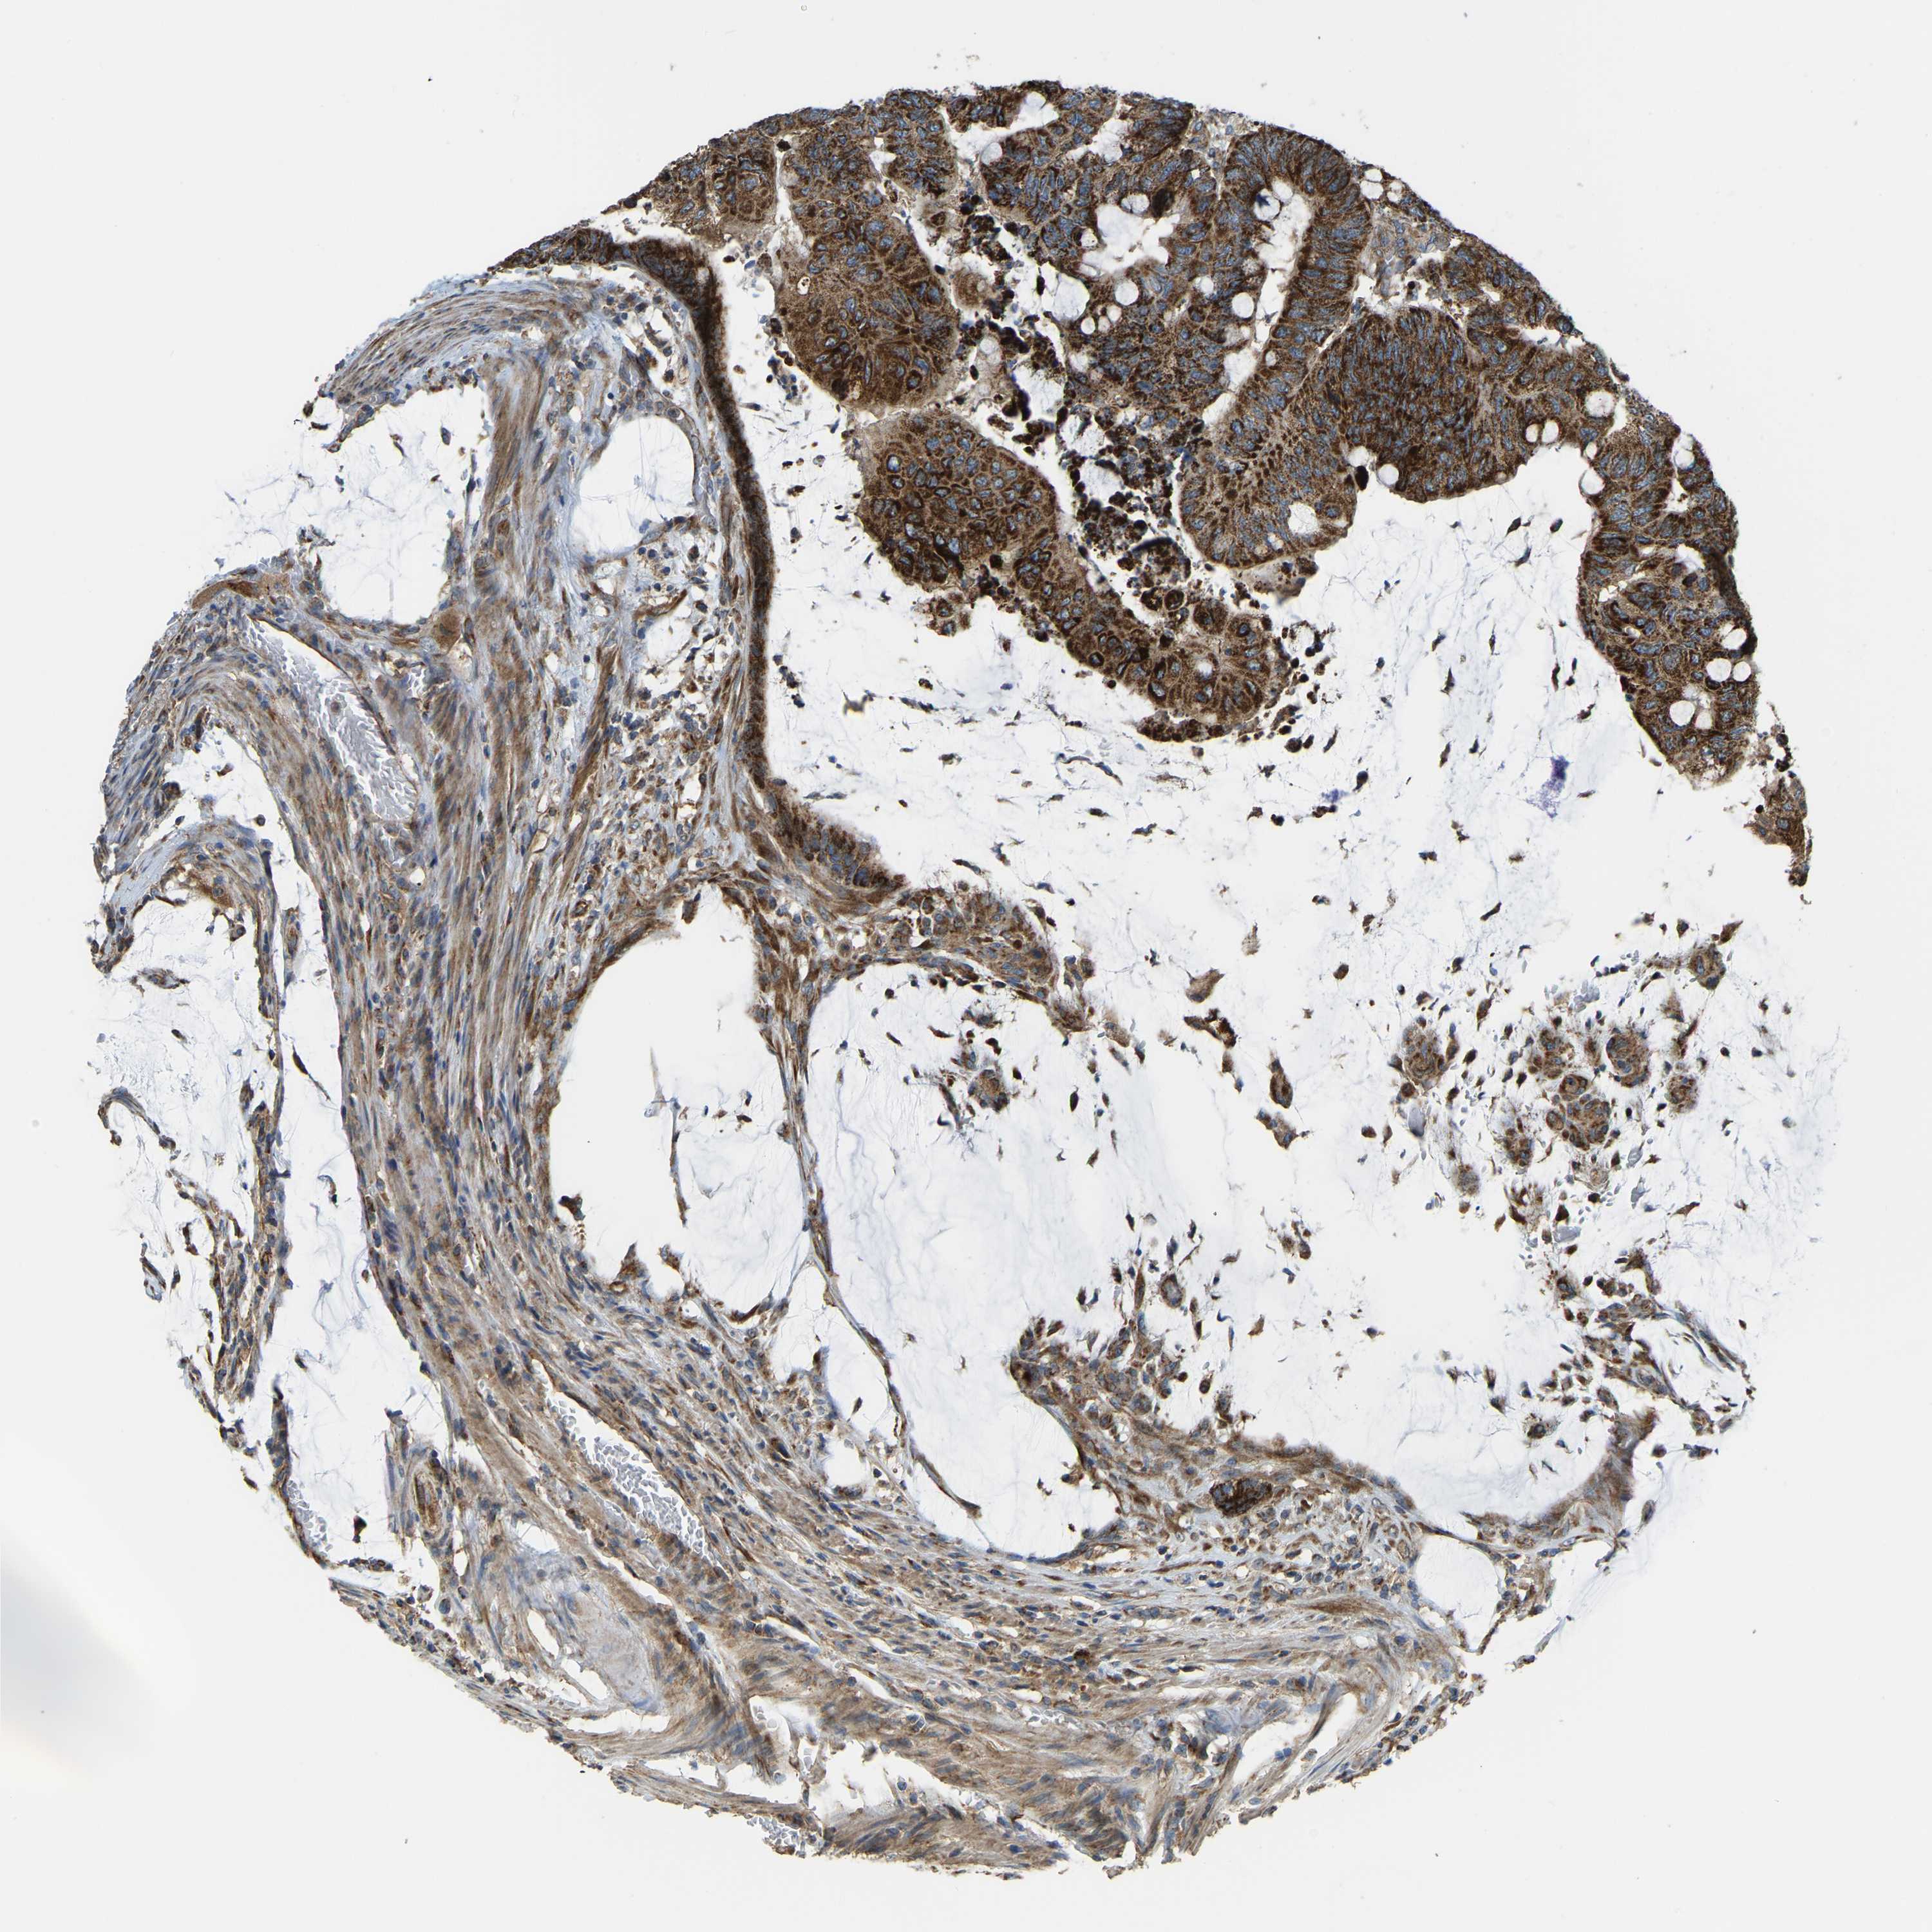

CANCER COLORECTAL CANCER Show tissue menu

Colorectal cancer

Human cancer

Colon adenocarcinoma